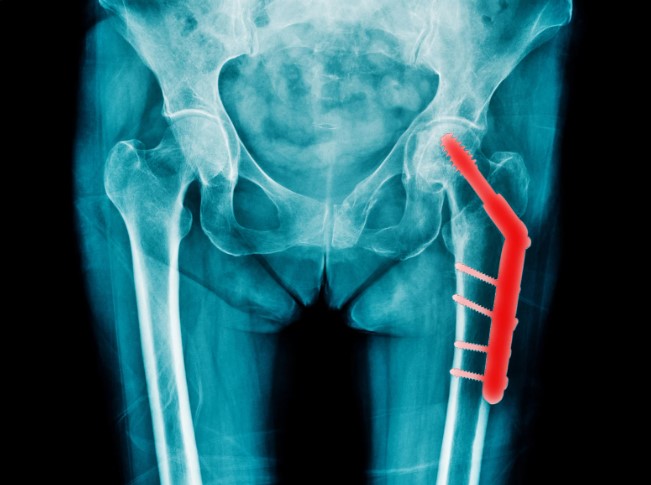

Hip replacement removes the damaged joint surfaces and replaces them with smooth, durable components that restore natural movement. Once the rough bone surfaces are removed, pain dramatically decreases, and function improves. Patients often walk with greater ease, regain balance, and enjoy renewed strength during daily activities. The procedure provides long-term relief for advanced hip arthritis, especially when non-surgical options no longer work.

Tec Orthopedics offers the Direct Anterior Approach hip replacement, a modern technique recognized for faster recovery and less tissue disruption. This method avoids cutting through major muscles, allowing patients to walk earlier with reduced discomfort. Benefits such as fewer movement restrictions, greater stability, and quicker return to routine activities make DAA an appealing option for many candidates seeking renewed mobility.